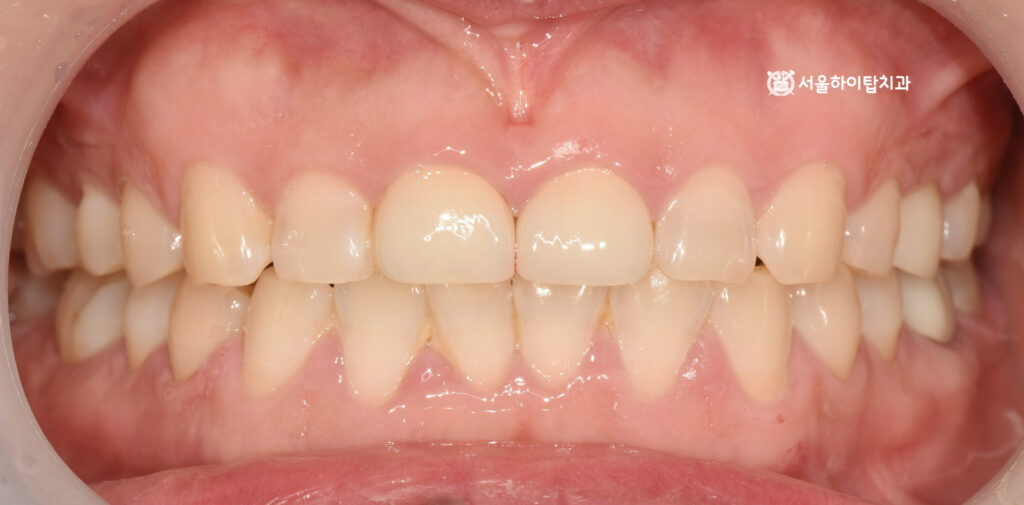

최종 사진을 통해 확인해 보면,

기존 자연치들 역시 평균치보다 치관 길이가 짧은 편이었기 때문에

이에 맞춰 크라운을 제작·장착하여 주변 치아와 자연스럽게

조화를 이루는 모습을 확인할 수 있습니다.

또한 기능적인 측면에서도 교합 접촉이 조절되면서,

전치부에 과도하게 가해지던 힘이 완화된 것으로 판단됩니다.

이를 통해 추가적인 교모나 파절 위험을 줄이고,

장기적으로 안정적인 교합 상태를 유지할 수 있는

기반을 마련한 것으로 볼 수 있습니다.